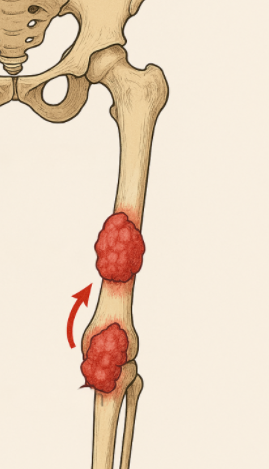

Bone sarcomas are more common in children, adolescents, and young adults. Presenting symptoms are location dependent, but commonly include mass, pain, swelling, fracture, compressed nerves, and weight loss. Skip metastasis are separate tumors found within the same bone (more common) or across a joint space; they’re rare and typically found with osteosarcomas. The presence of skip metastasis (mets) carries a worse prognosis.

- Figure 1; skip mets sarcoma © Jared Stiles

separate tumors found within the same bone or across a joint space; typically found with osteosarcomas